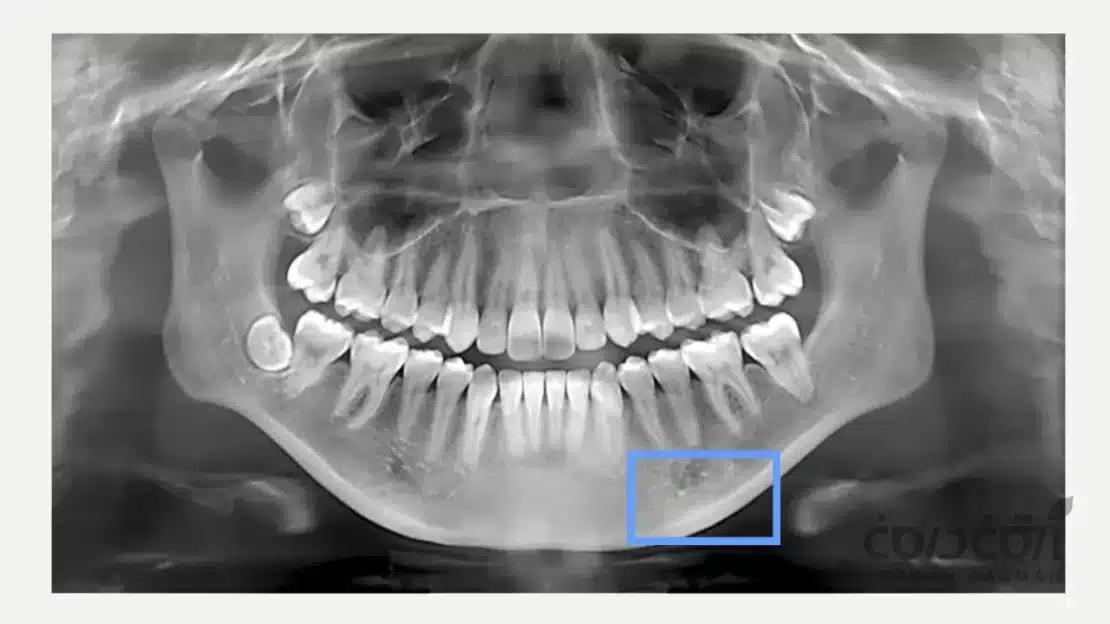

پس از، از دست دادن دندان، استخوان فک به مرور زمان تحلیل می رود (Resorption). در بسیاری از بیماران سالمند که سال ها بی دندان بودهاند، ممکن است حجم استخوان برای قرار دادن ایمپلنت دندان کافی نباشد.

ولی خب این یک مانع دائمی نیست. امروزه با تکنیک های بسیار قابل پیش بینی بازسازی هدایت شده استخوان (Guided Bone Regeneration – GBR) یا پیوند استخوان، می توانیم بستر استخوانی لازم را برای کاشت موفقیت آمیز ایمپلنت فراهم کنیم.